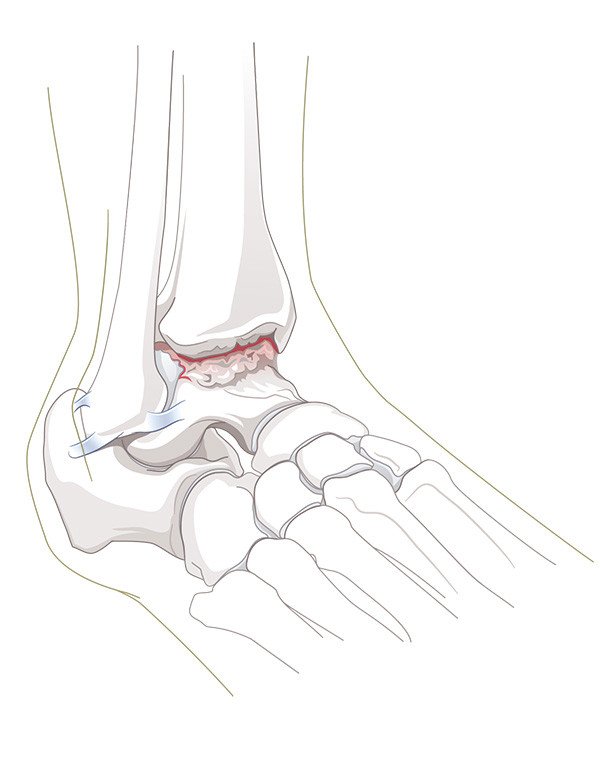

Das obere Sprunggelenk bildet die bewegliche Verbindung zwischen dem Unterschenkel (Schienbein und Wadenbein) und dem Sprungbein (Talus). Die Beweglichkeit des Rückfusses ist aber nicht nur durch dieses eine Gelenk gegeben, sondern durch die Summe eines komplexen Zusammenspiels sämtlicher Rückfussgelenke. Die zunehmende Abnützung des Gelenkknorpels, als Folge eines Unfalls oder im Rahmen einer entzündlichen Gelenkerkrankung, führt zur Arthrose im betroffenen Gelenk. Schmerzen und Bewegungseinschränkung sind die Folgen.

Diagnose

Links: Frontansicht

Rechts: Seitenansicht